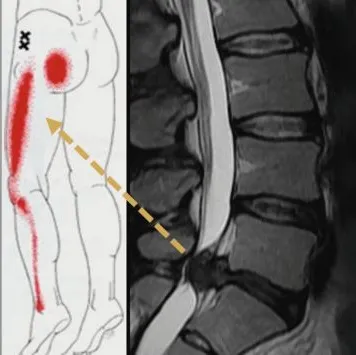

⚡ 從下背痛到腳麻:坐骨神經痛的警訊

單純的椎間盤受損可能只會感到下背痠痛(類似閃到腰)。但真正的惡夢開始於突出的髓核壓迫到後方的神經根。

這會導致疼痛沿著坐骨神經的路徑,一路從臀部、大腿後側放射至小腿甚至腳底。患者常形容這種痛感為「酸、麻、刺痛、像被電到」。若壓迫過久,甚至會出現肌肉萎縮、腳踝無力(垂足)等現象。最嚴重的情況稱為「馬尾症候群 (Cauda Equina Syndrome)」,會影響大小便功能(失禁或尿不出來),這時就必須緊急開刀,否則會造成永久性神經損傷。

2. 黃金標準:核磁共振 (MRI)

若症狀經過復健治療未改善,或是出現肌肉無力等嚴重神經學症狀,我們會建議安排 MRI 檢查。MRI 可以清晰地顯影出軟組織,讓我們看到椎間盤突出的確切位置、大小,以及神經根被壓迫的嚴重程度,這是評估是否需要手術的關鍵依據。